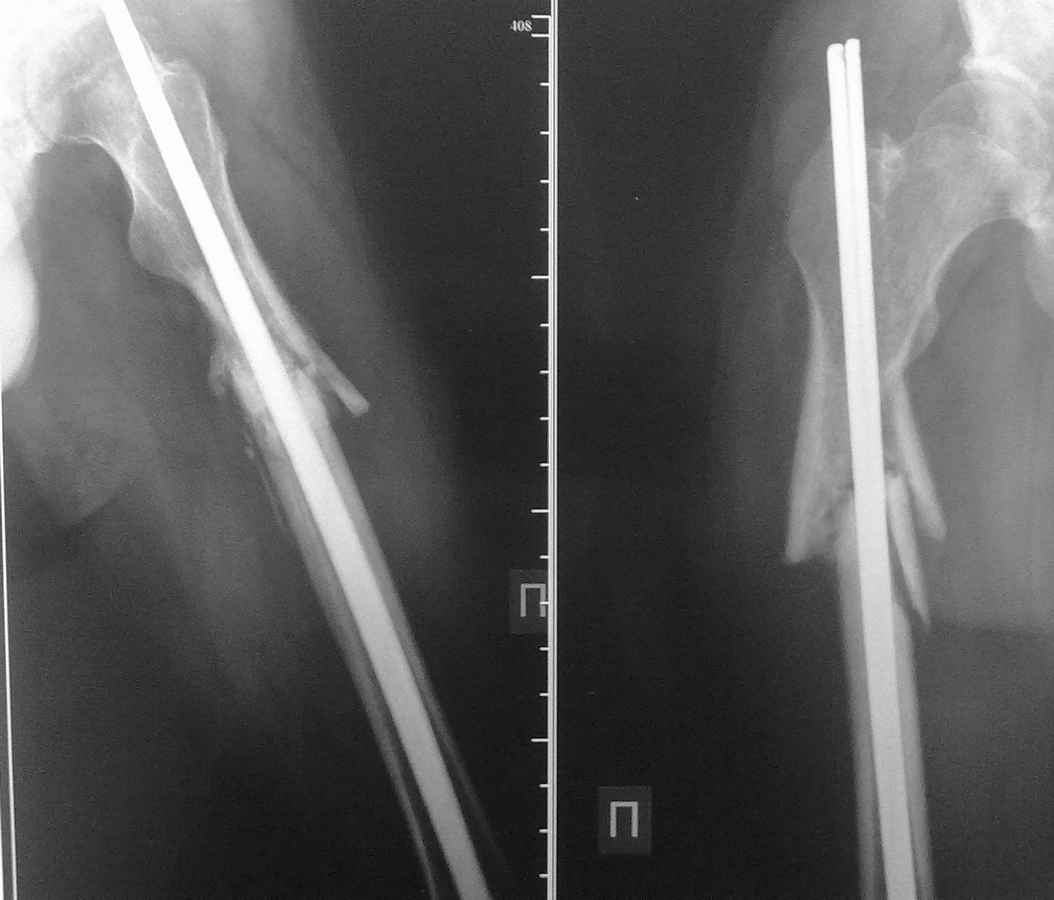

у пациента 24 лет после перелома бедра в ноябре 10г. и остеосинтеза двумя титановыми стержнями наступило вторичное смещение отломков и миграция стержней, укорочение 5 см

посылаю Рг-граммы и прошу Вашего мнения по тактике дальнейшего лечения, имеются расхождения во мнениях...с уважением, Роман

Уважаемый Роман! Если бы у меня был ЭОП, я бы не удаляя стержней(могу ошибаться, но мне кажется - это титановые прямоугольные стержни типа Зверева-Ключевского(производства г.Рыбинск) - наложил бы дистрактор, по типу того, как делает А.Н. Челноков. Восстановил бы длину сегмента, а затем бы перештифтовал "нормальным" стержнем, не обязательно гамма. Естественно с исправлением оси. 2,5 - 3 месяца не срок, тем более, что на снимке признаков мозоли не видно.

Не "Зверева-Ключевского(производства г.Рыбинск)", а Ключевского-Зверева(производства г.Рыбинск). Стержни похожи на наши, но технология нет. Т.к. нет радиусного искривления гвоздя, выведения плоского стержня через большой вертел (по Звереву), да и не помешал бы серкляж. В данном наблюдении все сделано как говорится "гвоздь в кость". А с тактикой согласен полностью

Добрый вечер!Да это стержни прямоугольного сечения, "почти" Ярославский МОС-бюджетный вариант. скажите а как быстро больной дал осевую нагрузку? почему произошло смещение?